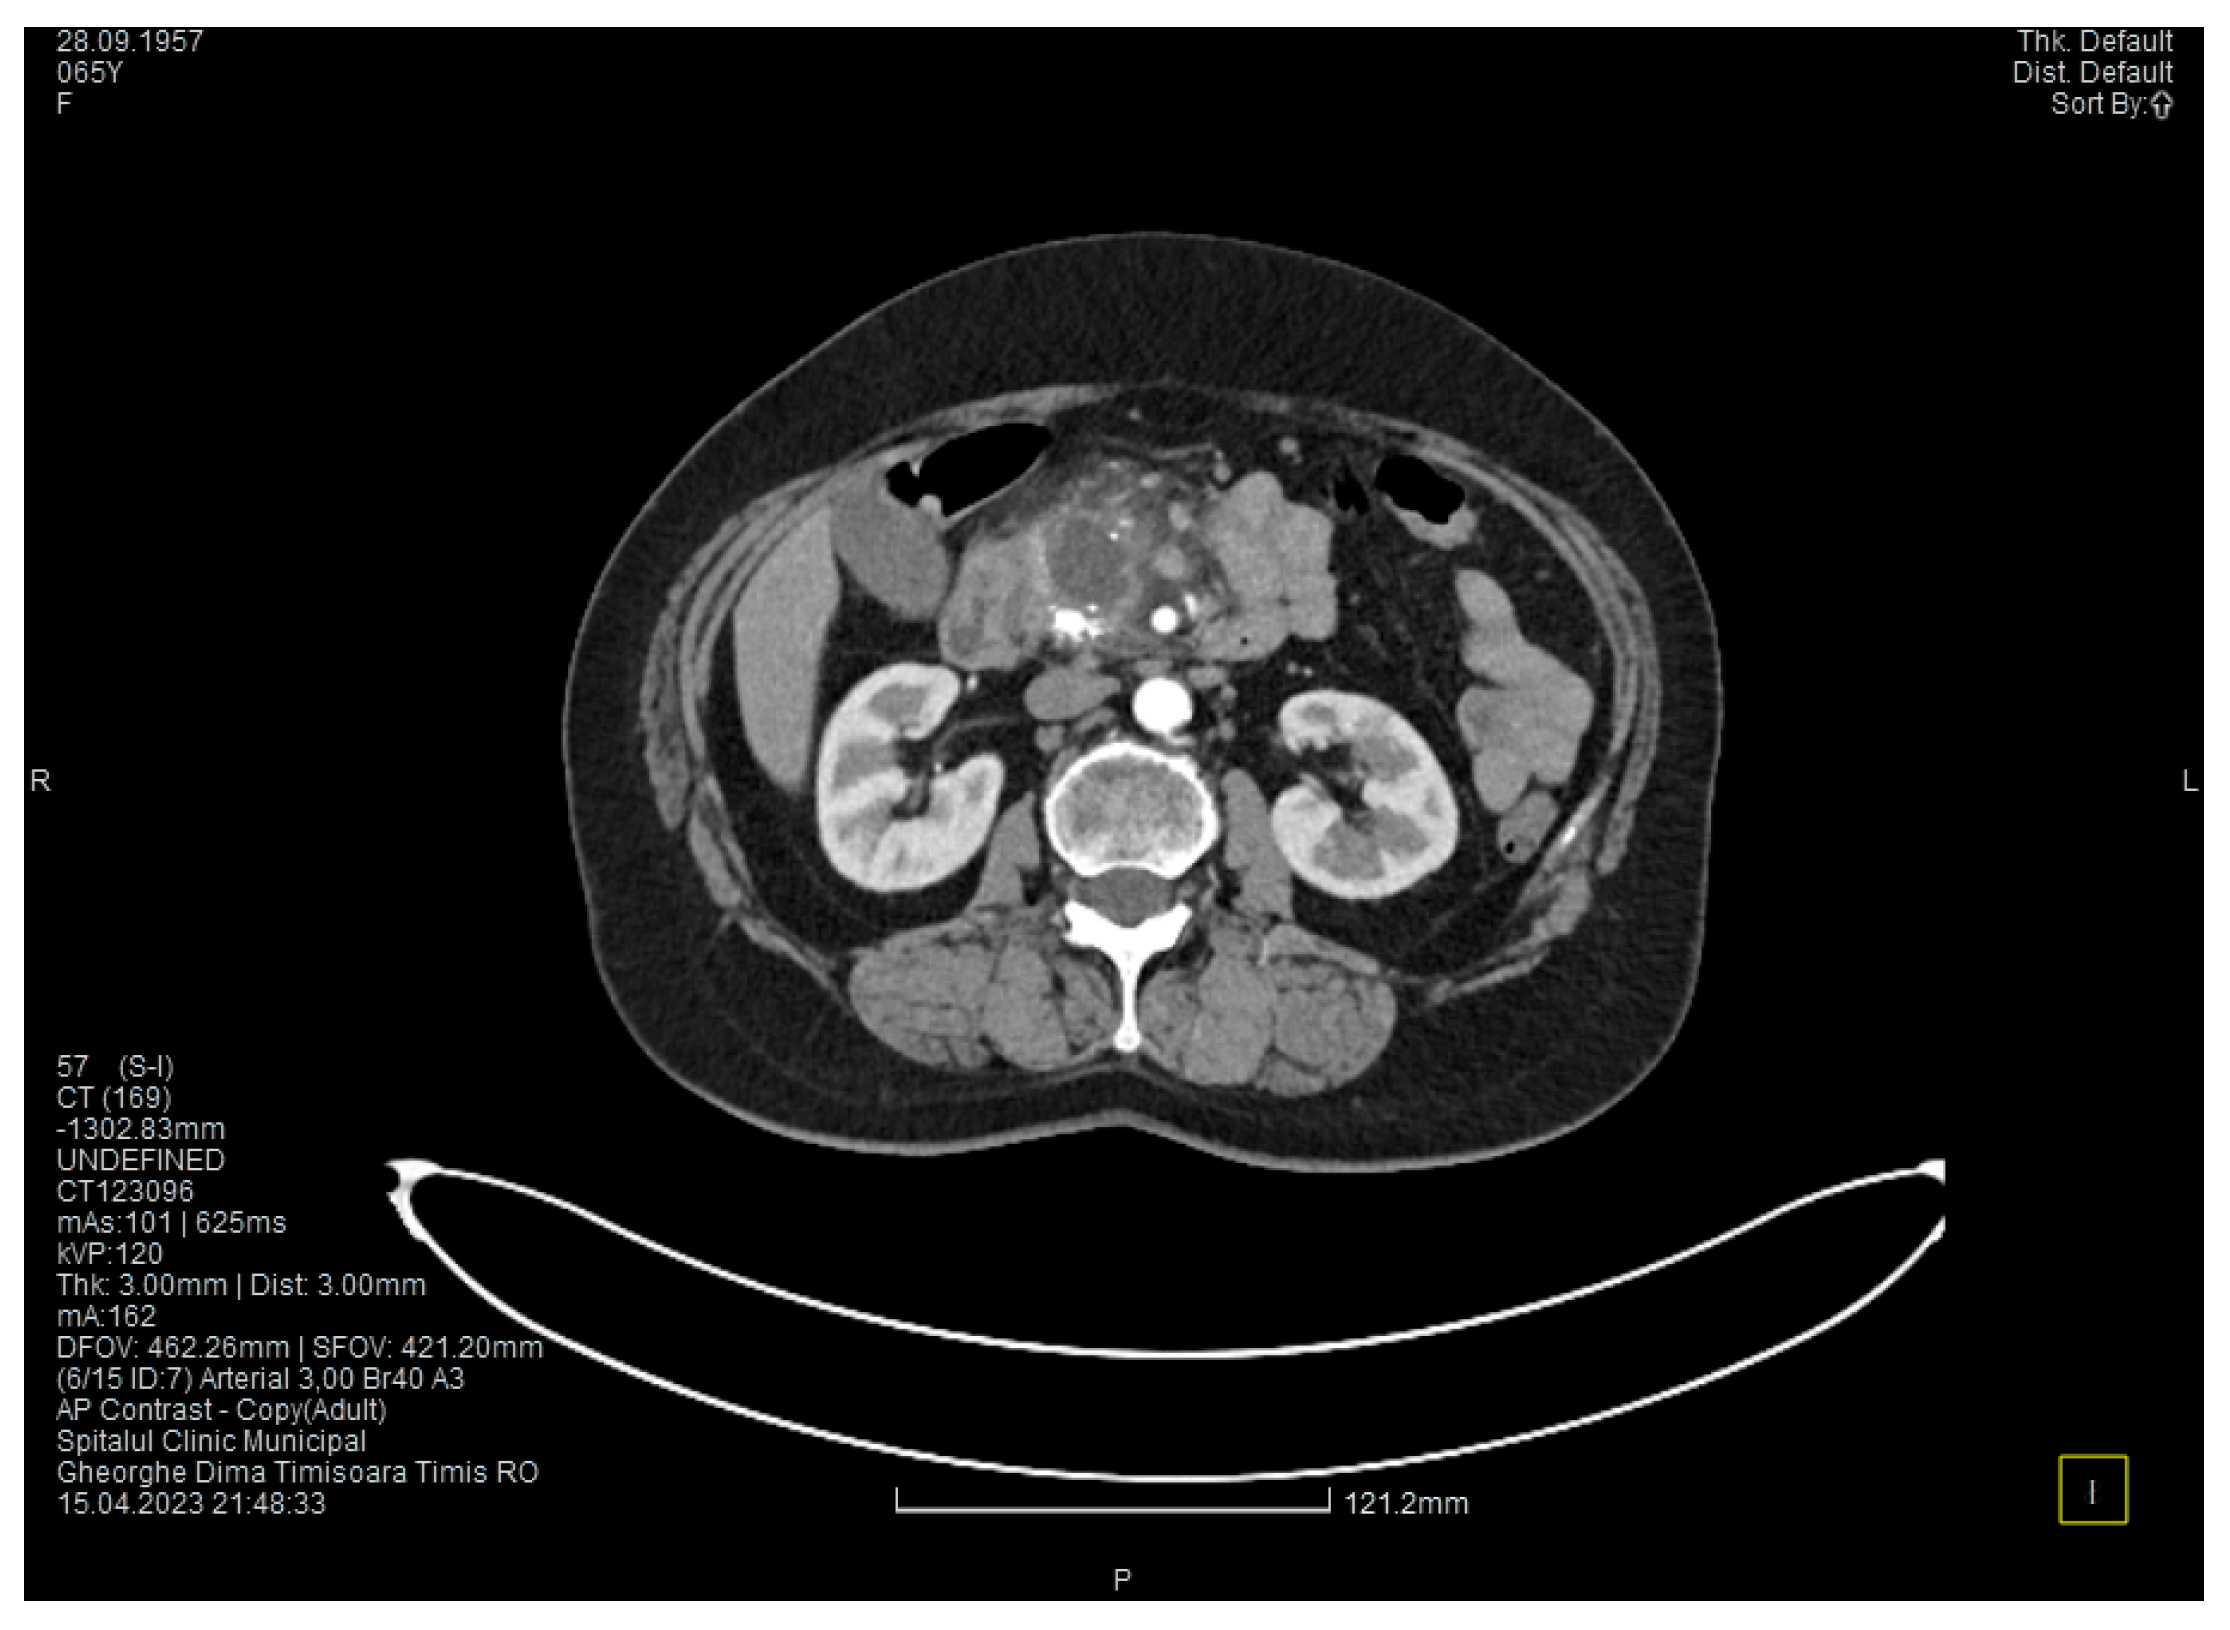

The contrast-enhanced computed tomography showed changes suggestive of chronic pancreatitis, with multiple very small calcifications of the pancreatic tissue, dilatation of the Wirsung duct in the corporeo-caudal area measuring approximately 15 mm (Figure 3), and a narrowing of the Wirsung tract in the cephalic area where calcareous conglomerates were present. In the anterior cephalo-uncinate area, an oval cyst measuring 31/28 mm was detected (larger than it was one month ago) (Figure 4). In the peri-cephalo-uncinate area, we observed densifications of the adjacent fat extending towards the gastric antrum, the root of the mesentery, and the hepatic flexure of the colon. There was a mild inflammatory enlargement of the peripancreatic lymph nodes and the ones situated in the hepatic hilum. We also noticed a slight dilatation of the intrahepatic bile ducts and the common hepatic duct, and diffuse atheromatosis of the aorta, the iliac, and the common hepatic arteries. We performed a gastroscopy, which revealed a normal esophagus, stomach, and duodenal bulb; however, it was impossible to advance the endoscope towards the D2 part of the duodenum due to the significant edema of the duodenal mucosa and the partial stenosis of the duodenal lumen.

Figure 3. The second CT evaluation shows a dilated Wirsung duct and calcifications in the pancreatic tissue.